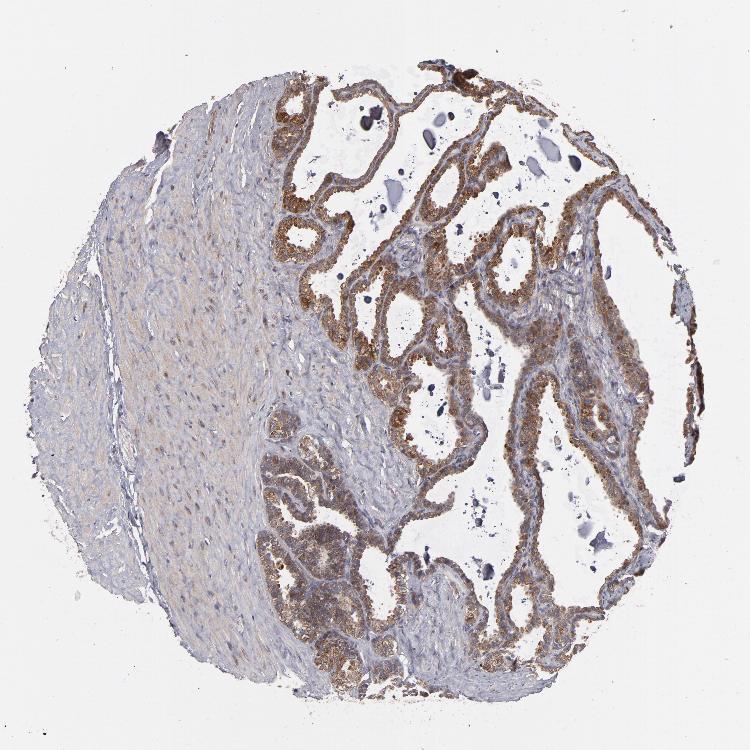

TISSUE PRIMARY DATA SEMINAL VESICLE Show tissue menu

SEMINAL VESICLE - Antibody stainingi

Antibody staining in the annotated cell types in the current human tissue is reported as not detected, low, medium, or high, based on conventional immunohistochemistry profiling in selected tissues. This score is based on the combination of the staining intensity and fraction of stained cells.

Each image is clickable and will lead to virtual microscopy that enables deeper exploration of all samples and also displays staining intensity scores, fraction scores and subcellular localization as well as patient and tissue information for each sample.

Antibody HPA002529Antibody HPA002632Antibody CAB019323

Glandular cells MediumHighHigh